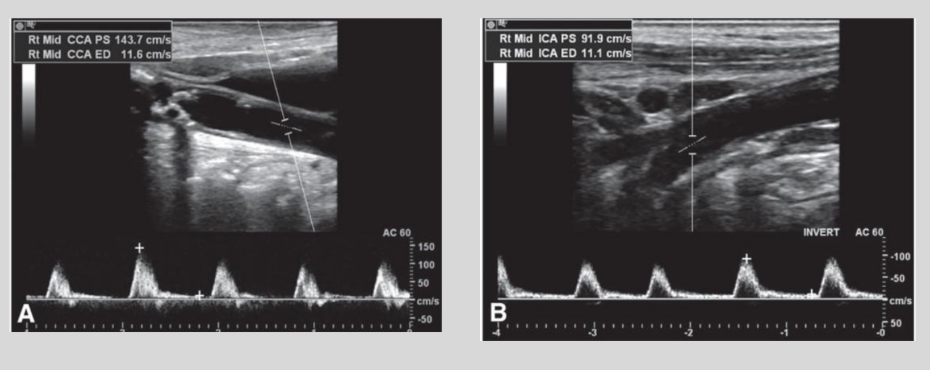

what is this waveform showing?

Bigeminy: irregular beat that

is followed by a normal beat